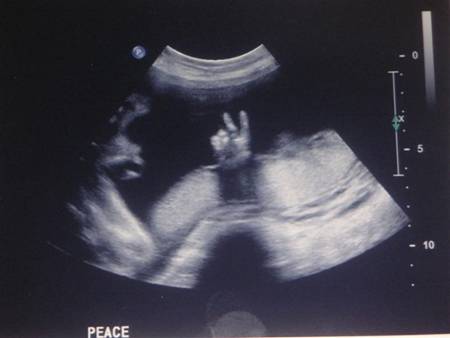

Nu mereu reușești să surprinzi atât de bine anumite imagini de ecograf. Tocmai de aceea, imaginile prezentate sunt foarte RARE!

De-a lungul timpului au fost surprinse mai multe imagini de ecograf cu adevărat uluitoare!

Iată mai jos 10 imagini de ecograf unice!